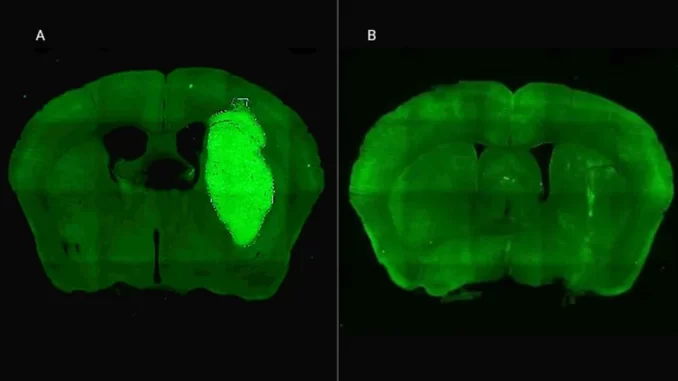

Al bloquear la proteína Foxp3 con un péptido experimental denominado P60, los científicos lograron que las células cancerosas respondieran mejor a los tratamientos habituales y, además, disminuyeran su capacidad de propagarse. Este hallazgo no solo detuvo el crecimiento del tumor en modelos preclínicos, sino que abre una puerta de esperanza para el desarrollo de futuras terapias combinadas en pacientes humanos.